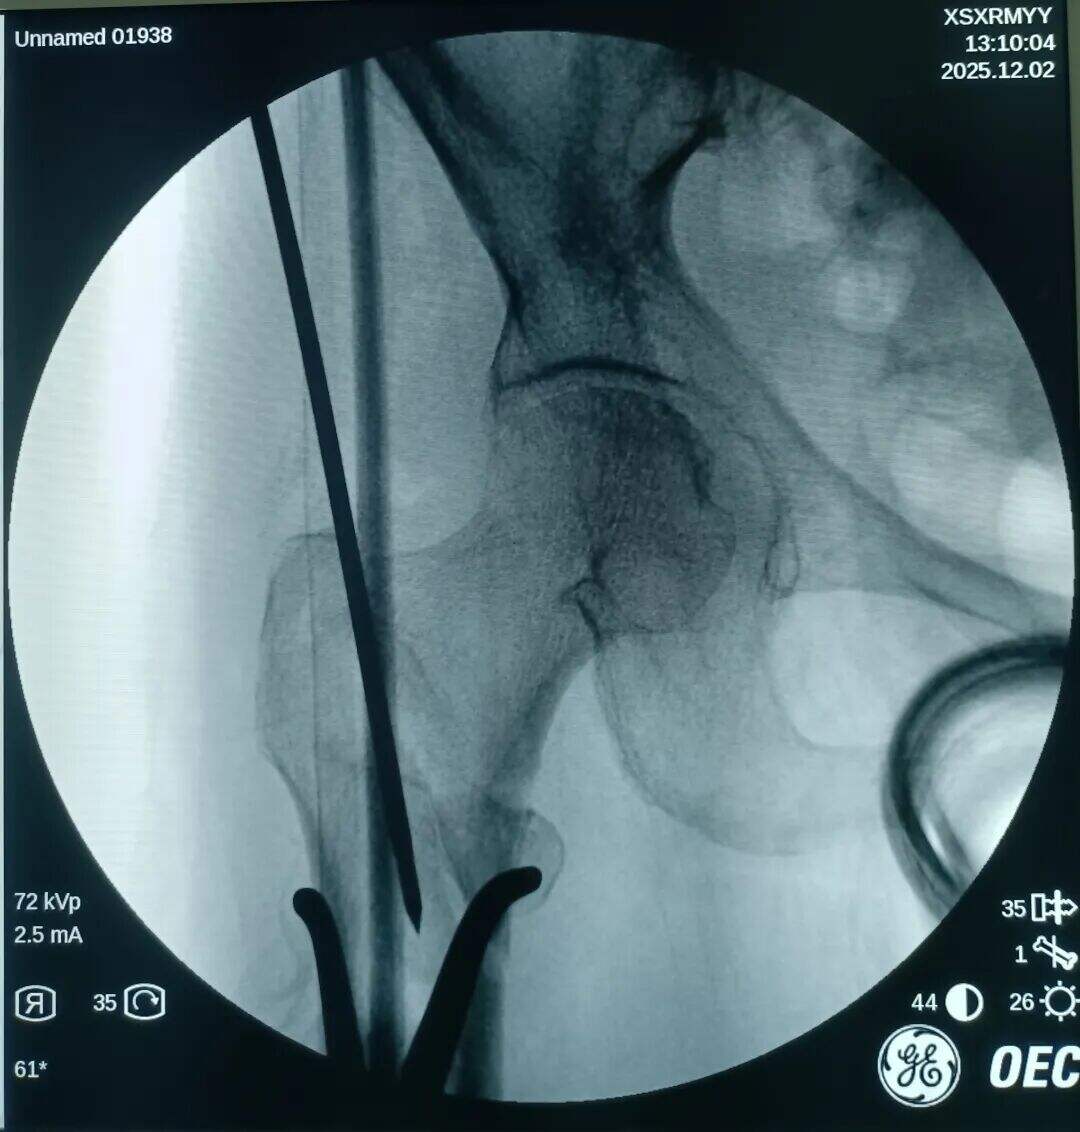

Starejša ženska, sprejeta po padcu.

Diagnoza: Pravi femoralni intertrohanterni zlom (AO razvrstitev tipa 31-A1.3).

Pri zlomih tipa 31-A1.3 je doseganje zadovoljive zmanjšanja vedno bilo izziv.

Poskus zaprta zmanjšanja, vendar ni uspel. Več vlečne sile je uporabljeno, več je bilo premaknjen v višji del zaradi vlečenja iliopsoas mišice.